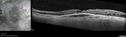

Pseudophakic cystoid macular edema (CME)158 views66 year old female 4 months following cataract surgery. Never had very good vision after surgery. On PF QID for one month. VA 20/50 in both eyes.